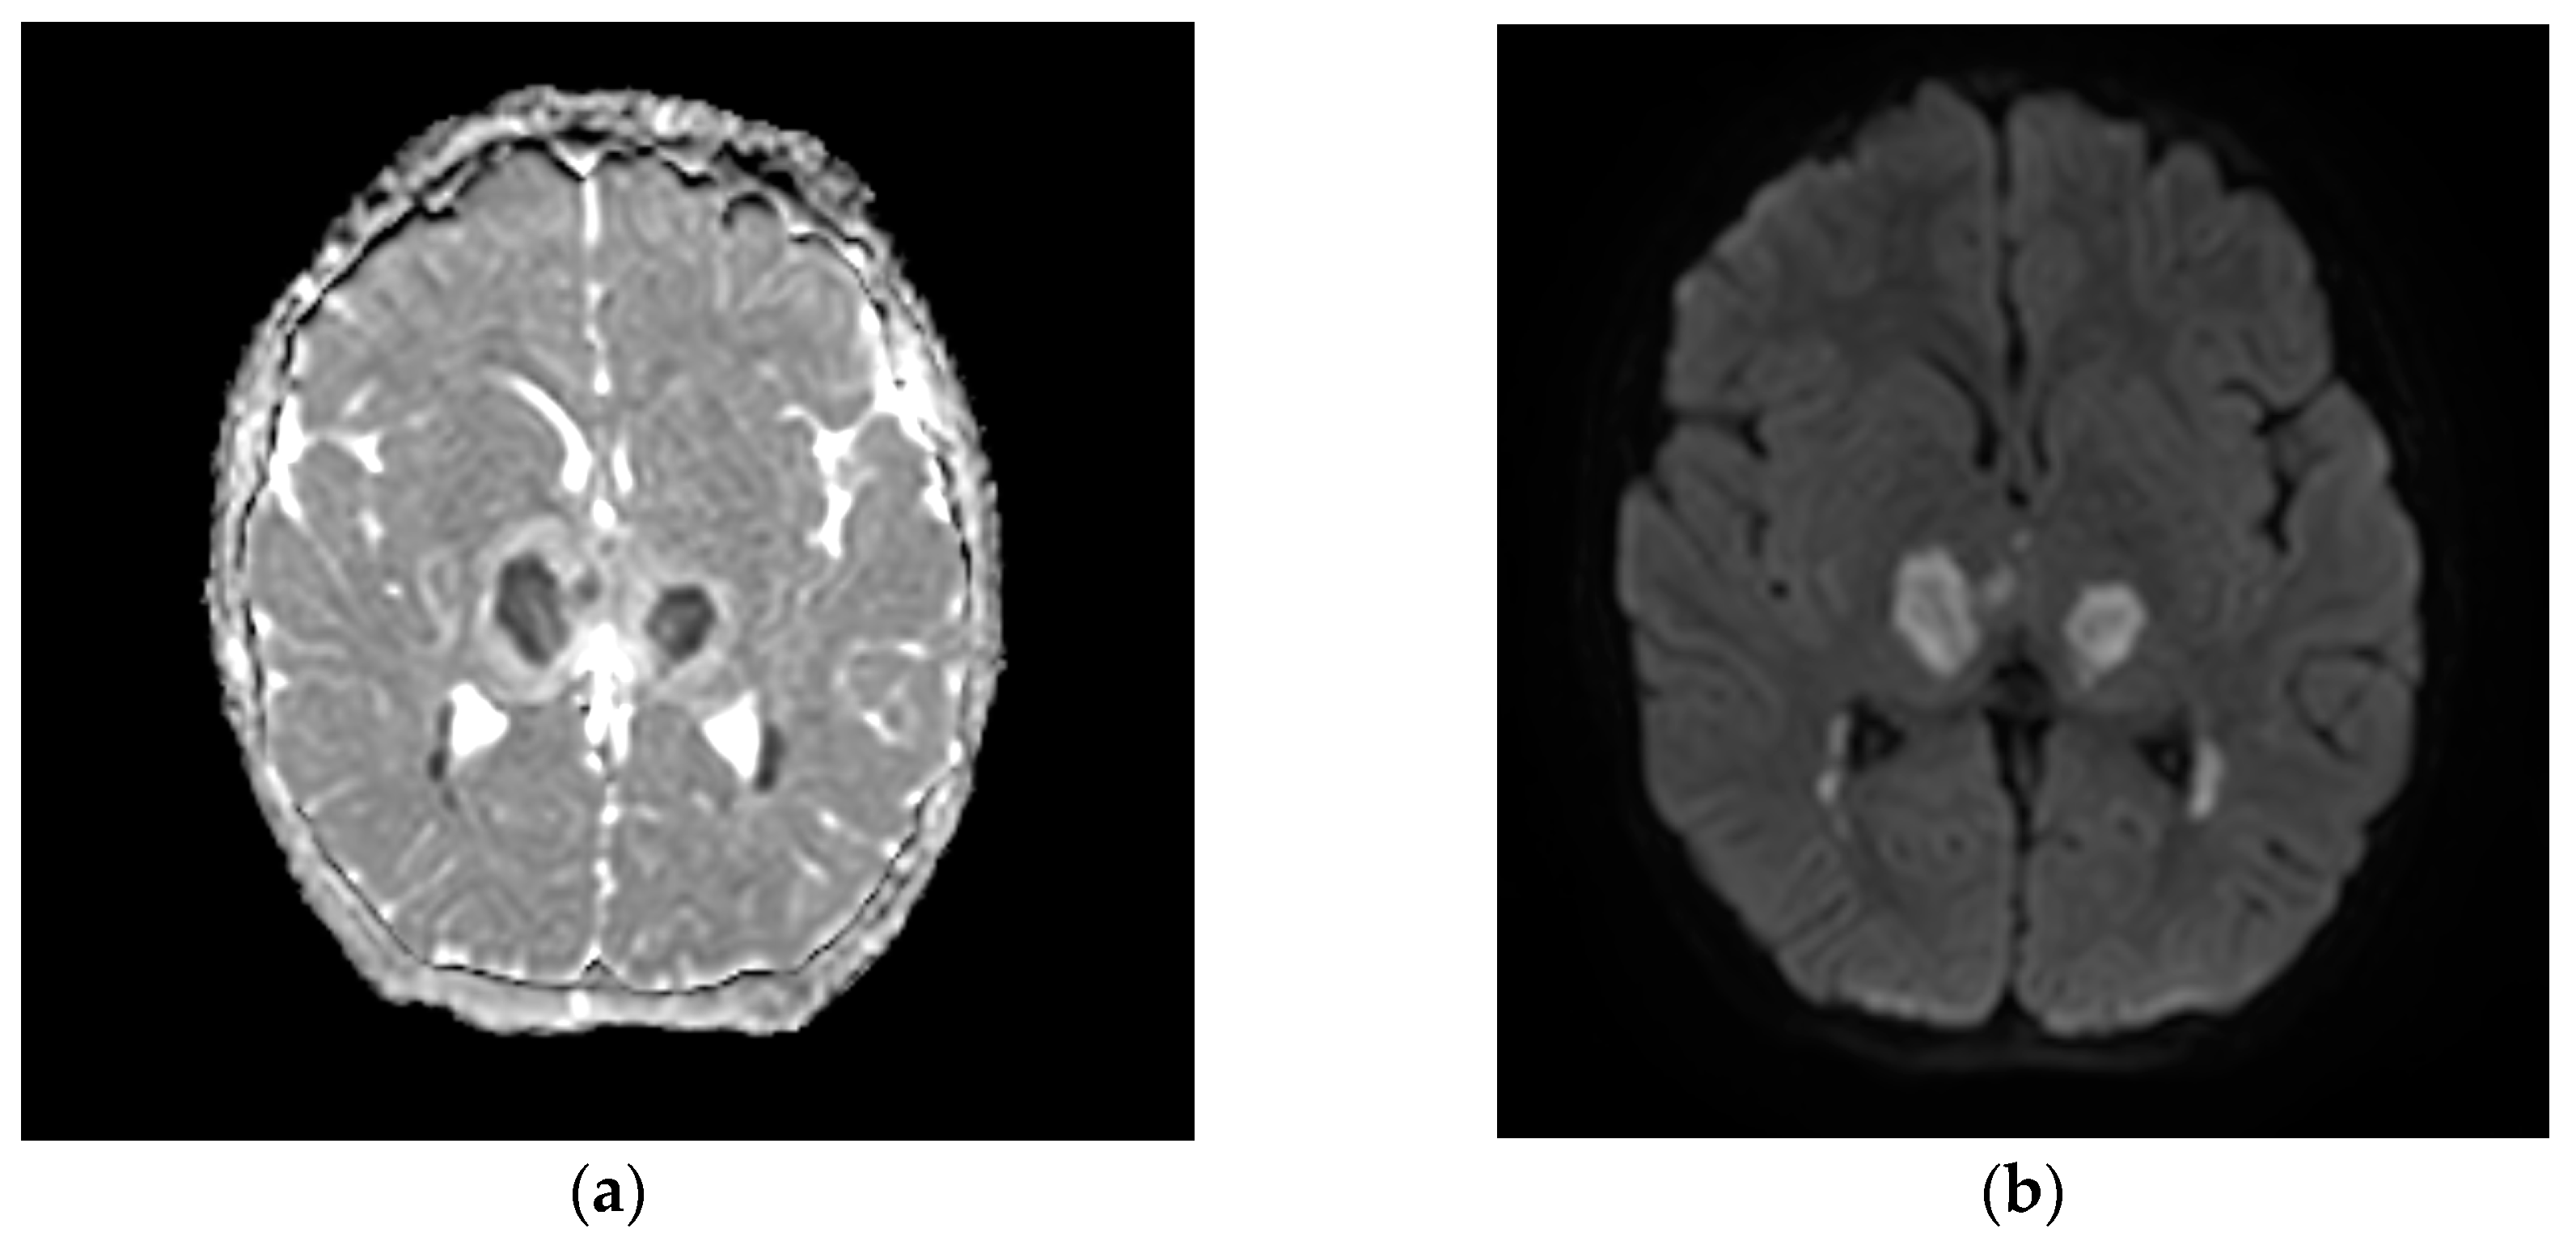

A neuropsychiatric evaluation and video EEG excluded seizures. Despite sedation being progressively weaned and then stopped, severe neurological deterioration persisted, with a GCS of 6. A brain MRI showed features compatible with ANE, including multiple localized signal hyperintensity in the T2/FLAIR sequences, especially in the cortico-subcortical frontal areas, in both thalami, in the cerebral peduncles, and the hemispheric and vermian parts of the cerebellum (Figure 1). The white matter of the semioval centers and putamen were involved as well. Diffusivity restriction, with low apparent diffusivity coefficient (ADC) values, was observed for cortical localizations in the precentral gyrus bilaterally, in the right middle frontal gyrus and right entorhinal cortex, in the semioval centers, and the peri trigonal, putaminal, thalamic, pontine tegmentum, cerebellar hemispheric, and vermian cortical and subcortical sites.

Figure 1. Typical MRI images of ANE in case 2: (a) low apparent diffusion coefficient (ADC) values; (b) restricted diffusion in the thalamus bilaterally.